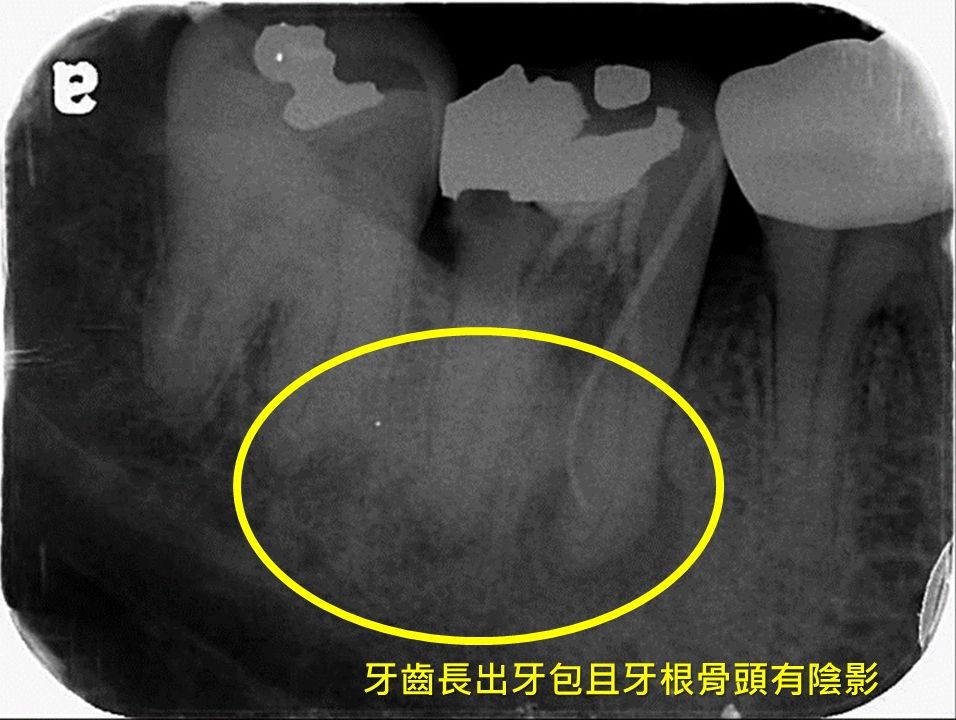

有民眾因牙齦長牙包至醫院求診,醫師診斷發現,牙齒已經抽過神經,但牙齒神經管內尚有殘餘的細菌,且牙齒再蛀牙、沒有進行很好的填補,造成細菌跟著口水再跑進神經管,進而擴散到牙根外的顎骨,細菌再沿著顎骨侵蝕到外面的牙齦,X光片上顯示牙根有陰影,確診為牙根膿腫,即是俗稱的牙包。

▲牙齦長出牙包且神經發炎壞死。(圖/奇美醫學中心提供) 郭祉吟說,這類病患常常在診所檢查後,發現X光片上在牙根有陰影,或者是病人突然發現長出牙包,因而被轉診到醫院,進行根管治療再治療。

▲牙齒根管中不只有神經而已,還有血管及其他組織。(圖/奇美醫學中心提供) 最重要的是,要確保牙齒蛀牙和治療開口有緊密的封填,也就是管道開口的密封性要夠好,否則根管內的殘餘細菌沿著向下孳生到牙根底部往骨頭擴散,就會開始侵蝕牙根周圍的骨頭,而在X光檢查下會發現牙根出現一圈黑影。